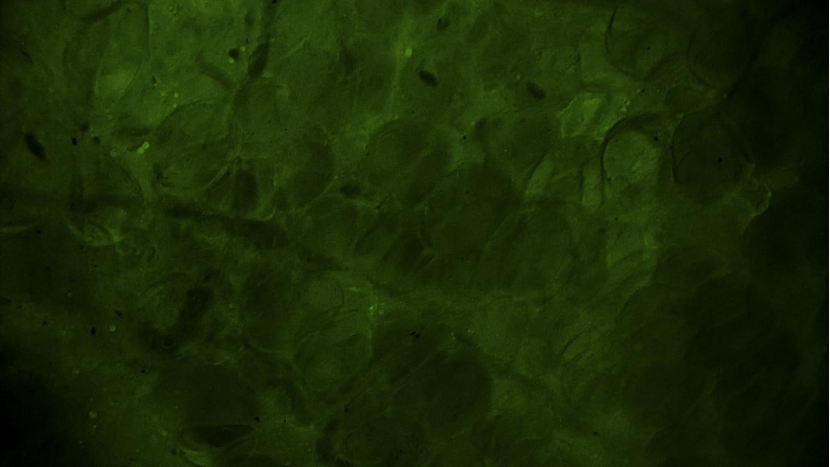

術(shù)中EndoSCell?細(xì)胞圖像如下:

脂肪組織:脂肪細(xì)胞規(guī)則透亮,分布均勻,未見(jiàn)腫瘤細(xì)胞